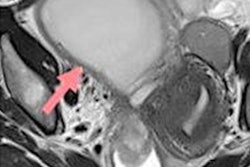

MRI can help further clarify and characterize abnormalities such as Müllerian duct anomalies, and it should be a second-line or adjunctive investigation to ultrasound in assessing fibroid disease and deep pelvic endometriosis, the authors stated.

Another type of subfertility is tubal pathology, which is the cause of subfertility in 25% to 35% of subfertile couples. Hysterosalpingo-contrast-sonography is a noninvasive way without ionizing resradiation to assess the cavity and tubal patency. The technique uses endovaginal ultrasound with simultaneous transcervical injection of ultrasound contrast agents or saline. It's performed during the midproliferative phase (days 6 to 10). The initial transvaginal ultrasound scan is carried out to assess the position of pelvic organs and rule out any pathology that would come in the way of the procedure. The reported sensitivity is 93.3%, and the specificity is 89.7% among experienced practitioners.